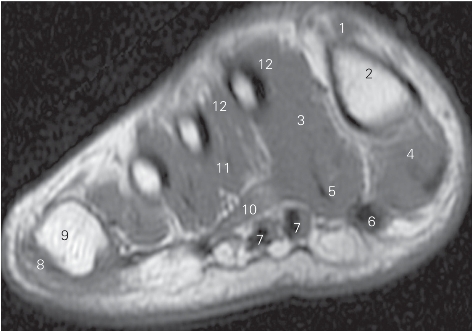

图5-53 经第一跖骨中份的横断层MR T1加权图像

1

长伸肌腱tendon of extensor hallucis longus

2 第一跖骨 1st metatarsal bone 3

收肌 adductor hallucis

4

展肌 abductor hallucis 5

短屈肌 flexor hallucis brevis

6

长屈肌 flexor hallucis longus 7 趾长屈肌 flexor digitorum longus

8 趾短屈肌 flexor digitorum brevis 9 足底腱膜 plantar fascia

10 小趾短屈肌 flexor digiti minimi brevis

11 小趾展肌 abductor digiti minimi 12 第四跖骨 4th metatarsal bone

13 骨间背侧肌 dorsal interossei